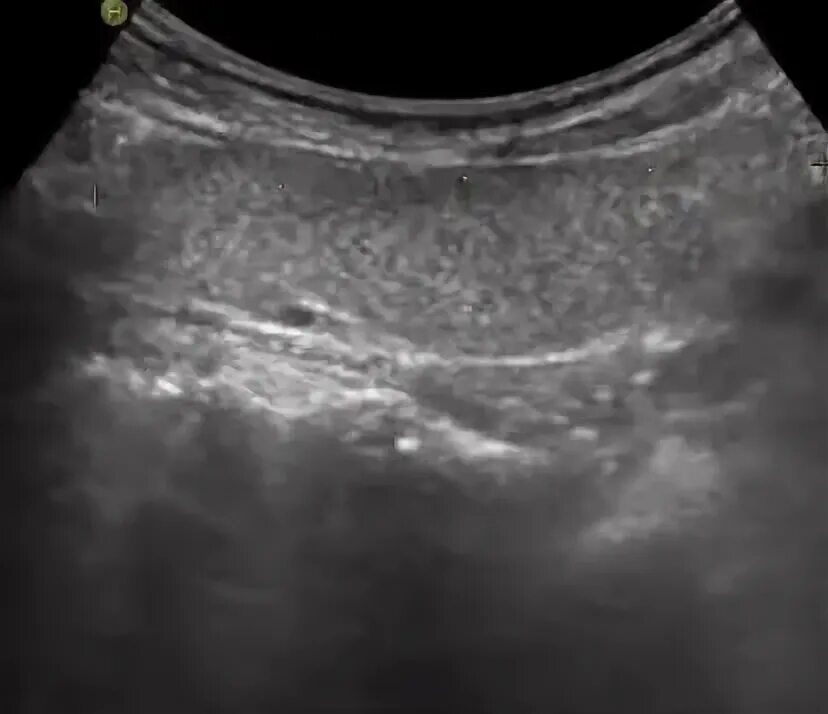

Выраженные диффузные изменения щитовидной железы